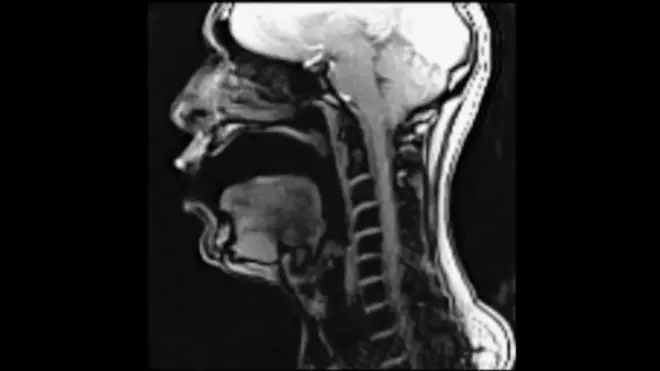

VIDEO - Que se passe-t-il à l'intérieur de la gorge d'un chanteur ? La réponse grâce à une IRM

Afin de comprendre comment fonctionnent la langue, le larynx et les muscles de la parole, un artiste lyrique a chanté pendant qu'il passait une IRM.

Qui n’a pas rêvé d'observer le fonctionnement des organes de la voix ? Grâce à Tyley Ross, un chanteur new-yorkais, c’est désormais possible. Il a passé une IRM pour observer ce qui se passe à l'intérieur de sa gorge et de sa tête lorsqu’il utilise différentes techniques de chant.

Dans cette vidéo en anglais, il chante d’abord dans ce que l’on appelle la voix de tête, puis la voix de poitrine. Il utilise ensuite une technique d’opéra et enfin une technique de rock.

On remarque de grandes différences dans le positionnement de la langue, des lèvres, du larynx et des cordes vocales lorsqu’il passe d'une technique à l'autre. Cela n’a pas manqué d’intéresser ce doctorant, dont le sujet de thèse porte sur la langue :